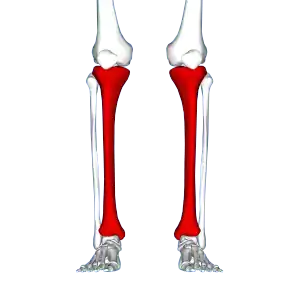

Red area represents the tibia. Pain is generally in the inner and lower 2/3rds of tibia.

A shin splint is pain along the inside edge of the shinbone (tibia) due to inflammation of tissue in the area.[1] Generally this is between the middle of the lower leg to the ankle.[2] The pain may be dull or sharp and is generally brought on by exercise.[1] It generally resolves during periods of rest.[3] Complications may include stress fractures.[2]

Shin splint pain is described as a recurring dull ache, sometimes becoming an intense pain, along the inner part of the lower two-thirds of the tibia.[4] The pain increases during exercise, and some individuals experience swelling in the pain area.[5] In contrast, stress fracture pain is localized to the fracture site.[6]